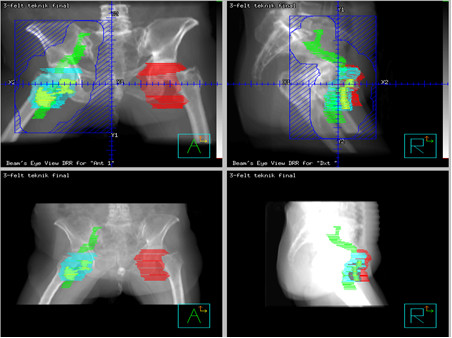

Na poniższej rycinie przedstawiono plan konformalnego napromieniania węzłów chłonnych. Którego z nowotworów narządu rodnego może ta sytuacja dotyczyć?

Na poniższych rycinach przedstawiono rozkład izodoz i zaznaczono obszar PTV u chorej napromienianej z powodu raka szyjki macicy. Jakie techniki wykorzystano w planowaniu leczenia na rycinach po lewej i po prawej stronie?

Lewa Prawa